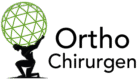

Anatomie des Kniegelenks: Links normale Position der Kniescheibe, rechts Patellaluxation mit seitlicher Verschiebung

Bei einer Patellaluxation springt die Kniescheibe aus ihrer Führungsrinne am Oberschenkelknochen. Die Kniescheibe ist ein dreieckiger Knochen, der in die große Strecksehne der Oberschenkelmuskulatur eingebettet ist und normalerweise in einer v-förmigen Gleitrinne des Oberschenkelknochens verläuft. In den meisten Fällen (etwa 80%) springt die Kniescheibe zur Außenseite des Knies.